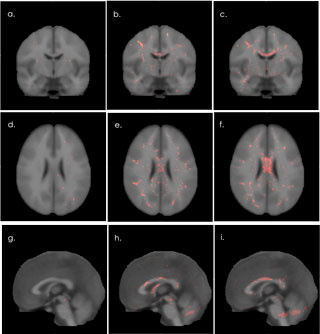

9 brain scans

Veterans of the mideast conflicts with mild TBI have measurable abnormalities in the white matter of their brains compared to returning veterans who have not experienced TBI. Image shows composite illustration of white matter potholes (red and yellow dots) in brains of veterans with probable TBI (column on the right), possible TBI (middle column and no TBI (column on the left)

Analysis of the DTI data allowed the researchers to detect areas of lower integrity in the patients' white matter even though these so-called potholes are scattered randomly throughout the brain and occur in different places in different patients.

Veterans with mild TBI had a significantly more potholes than veterans without TBI. The difference in the number of potholes was not influenced by age, time since trauma, a history of mild TBI unrelated to deployment, or coexisting psychological problems like depression, anxiety, or PTSD. The number of potholes did, however, correlate with poorer performance on cognitive tests measuring decision-making and planning skills.